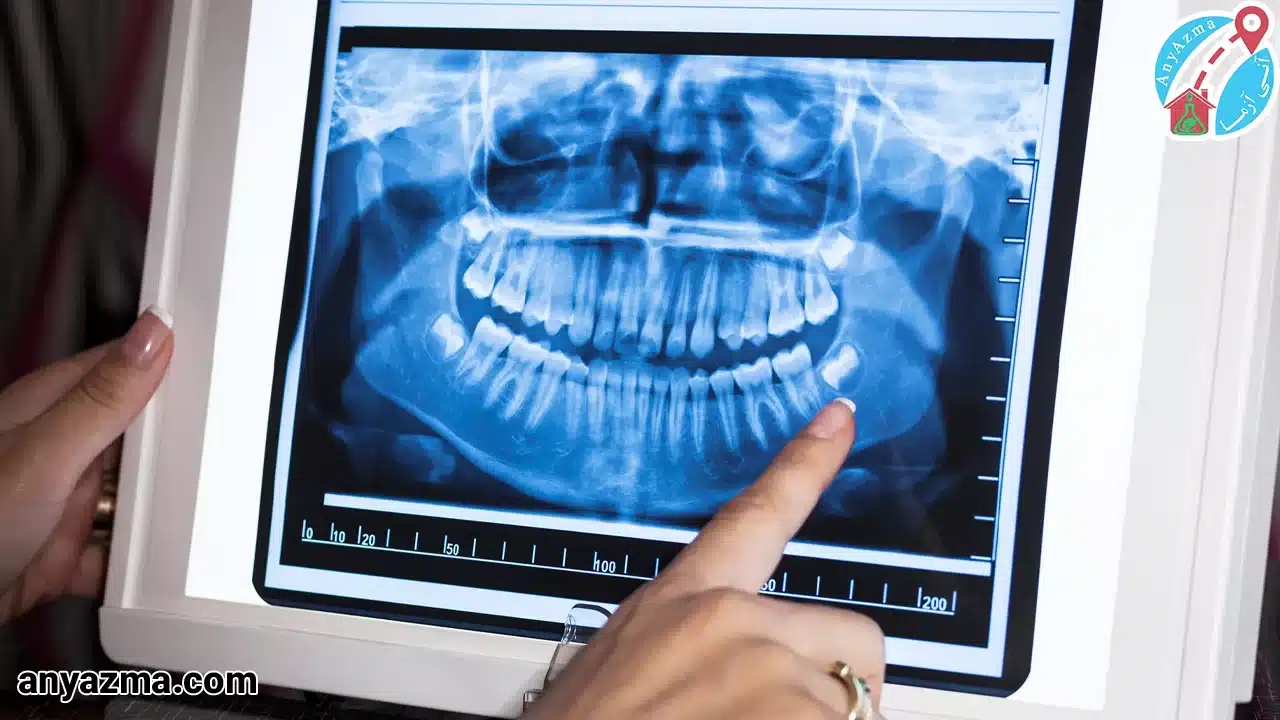

خدمات رادیولوژی فک و صورت در منزل از آنی آزما، برای تصویربرداری دقیق از ساختارهای پیچیده استخوانی فک، صورت و دندانها به کار میرود؛ برای انواع درمانهای دندانی، از ترمیم گرفته تا عصبکشی و حتی جراحی دندان عقل. رادیولوژی در منزل برای همه افراد قابل انجام است اما برای بیمارانی که امکان جابهجایی ندارند یا به دنبال صرفهجویی در زمان هستند، ضروری است. ما با استفاده از دستگاههای پرتابل پیشرفته (X-ray) و کارشناسان باتجربه، تصاویر با کیفیت و استانداردی را مستقیما در محل اقامت شما چه خانه و چه محل کار، تهیه میکنیم.

- تصویربرداری تخصصی: بسته به نیاز (مانند OPG یا نماهای تخصصی فکی)، تصویربرداری با حداقل دوز اشعه انجام میشود تا بهترین عکس رادیولوژی فک و صورت حاصل شود.

- دقت تشخیصی تضمین شده: دستگاههای مدرن پرتابل ما، تصاویری با وضوح و دقت معادل دستگاههای ثابت مراکز تخصصی ارائه میدهند.

بله، کاملا مشابه است. آنی آزما تنها از تجهیزات دیجیتال پرتابل پیشرفته استفاده میکند که توانایی تولید تصاویر با وضوح و رزولوشن مورد نیاز برای تشخیصهای تخصصی دندانپزشکی و جراحی فک و صورت را دارند.